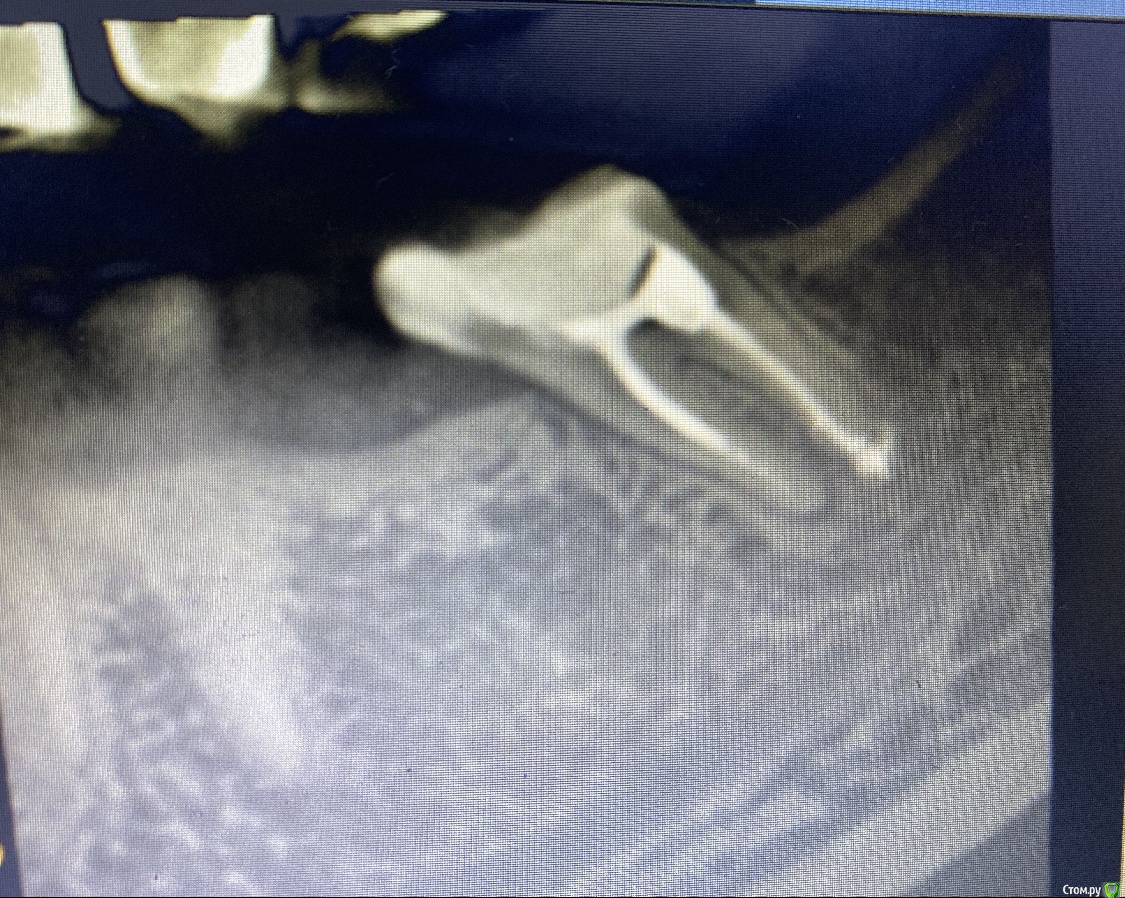

Sweet September Опубликовано 31 августа, 2020 Поделиться Опубликовано 31 августа, 2020 (изменено) Всем здравствуйте! Подскажите пожалуйста, смотрю на снимок, мне кажется или действительно материал вышел за верхушку корня? Месяц назад пломбировали, и неделю как болит, ни языком доторонуться не могу, не жевать этим зубом. Нижняя 7-ка Изменено 31 августа, 2020 пользователем Sweet September Ссылка на комментарий

St. Опубликовано 31 августа, 2020 Поделиться Опубликовано 31 августа, 2020 Да, материал немного вышел. Не страшно но не приятно в плане дискомфорта после пломбировки, может быть до месяца. Должно постепенно уменьшатся. Сейчас принимайте ибупрофен или нимесил если сильно беспокоит. Если же дискомфорт усилится, обратитесь к доктору для осмотра Ссылка на комментарий